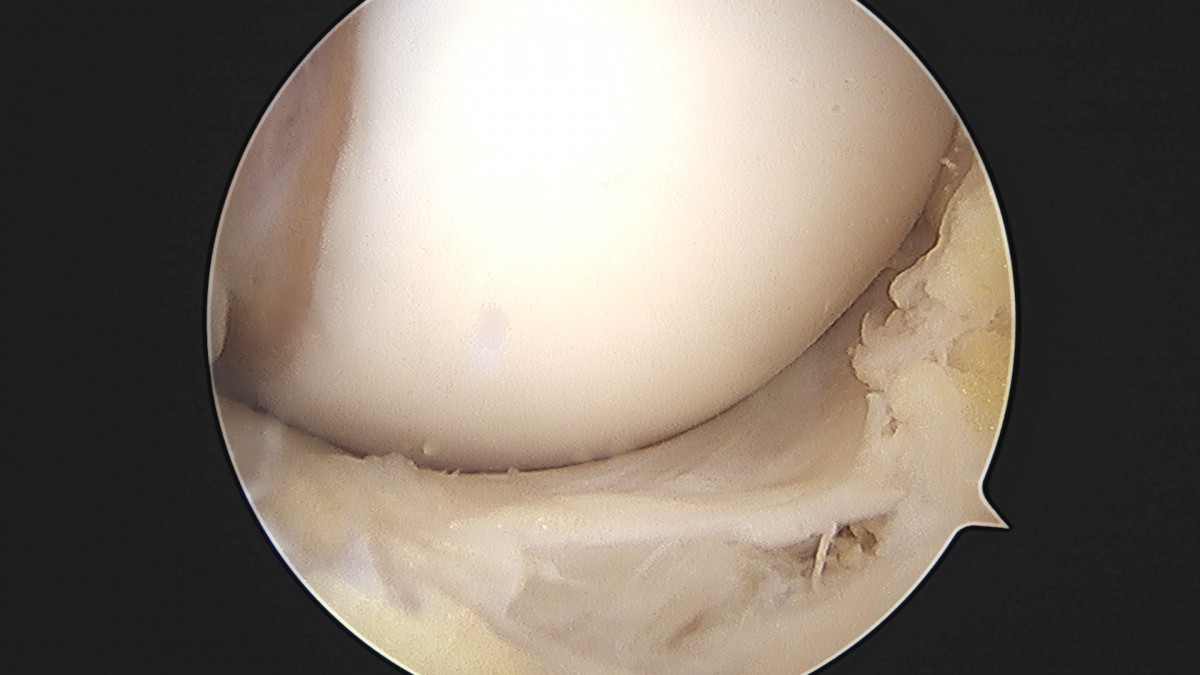

이재상원장님 무릎 낭종 제거술 김은O 환자

작성자 최고관리자 댓글 0건 조회 789회 작성일 25-09-16 15:20